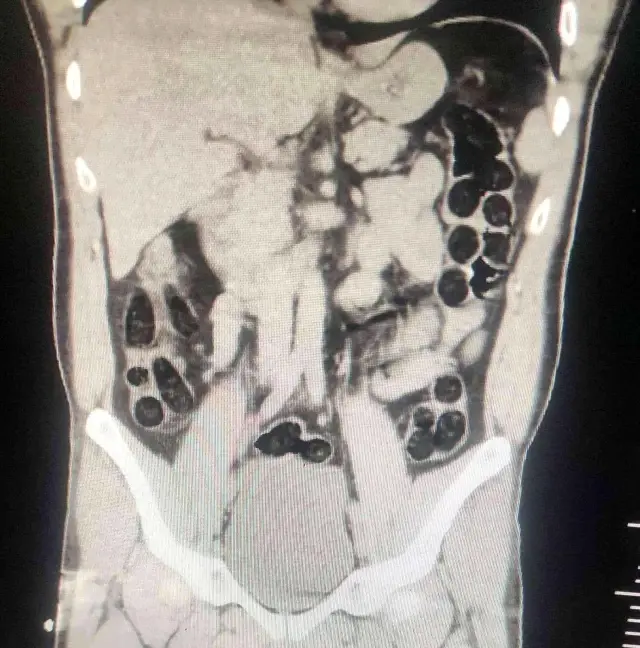

Operasyonda; otobüs ile seyahat eden 2 İran uyruklu şahsın yapılan kontrollerinde ve iç beden muayenesi sonucunda, şahıslardan birinin midesinde 76 paket halinde 714 gram uyuşturucu madde ele geçirildi.